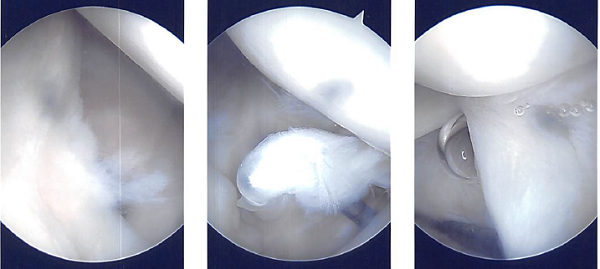

A beanbag held the position, and all of the bone prominences were well-padded. Behind the posterolateral corner of the acromion, a surgical incision was made. The glenohumeral joint was penetrated with the scope. There was a glenohumeral joint examination.

The labral hole was present. Labral degenerations were removed by shaving. The posterior labrum had degeneration, which was cleared out by shaving. There was subacromial bursitis.

Using a shaver, a thorough bursectomy was performed. It was created a lateral portal. The acromion was frayed and had a type 2 (curved configuration) configuration.

Acromioplasty was decided upon. After cleaning with a heat wand and a bur, acromioplasty was carried out. The AC joint was checked after a comprehensive acromioplasty and found to be degenerating. Excision of the distal clavicle was planned. The distal clavicle was removed using a wand and then a bur.

The distal clavicle’s last centimeter was removed. Final images were captured and stored. Nylon #4-0 was used for closure. After being extubated, the patient was taken to the recovery area.